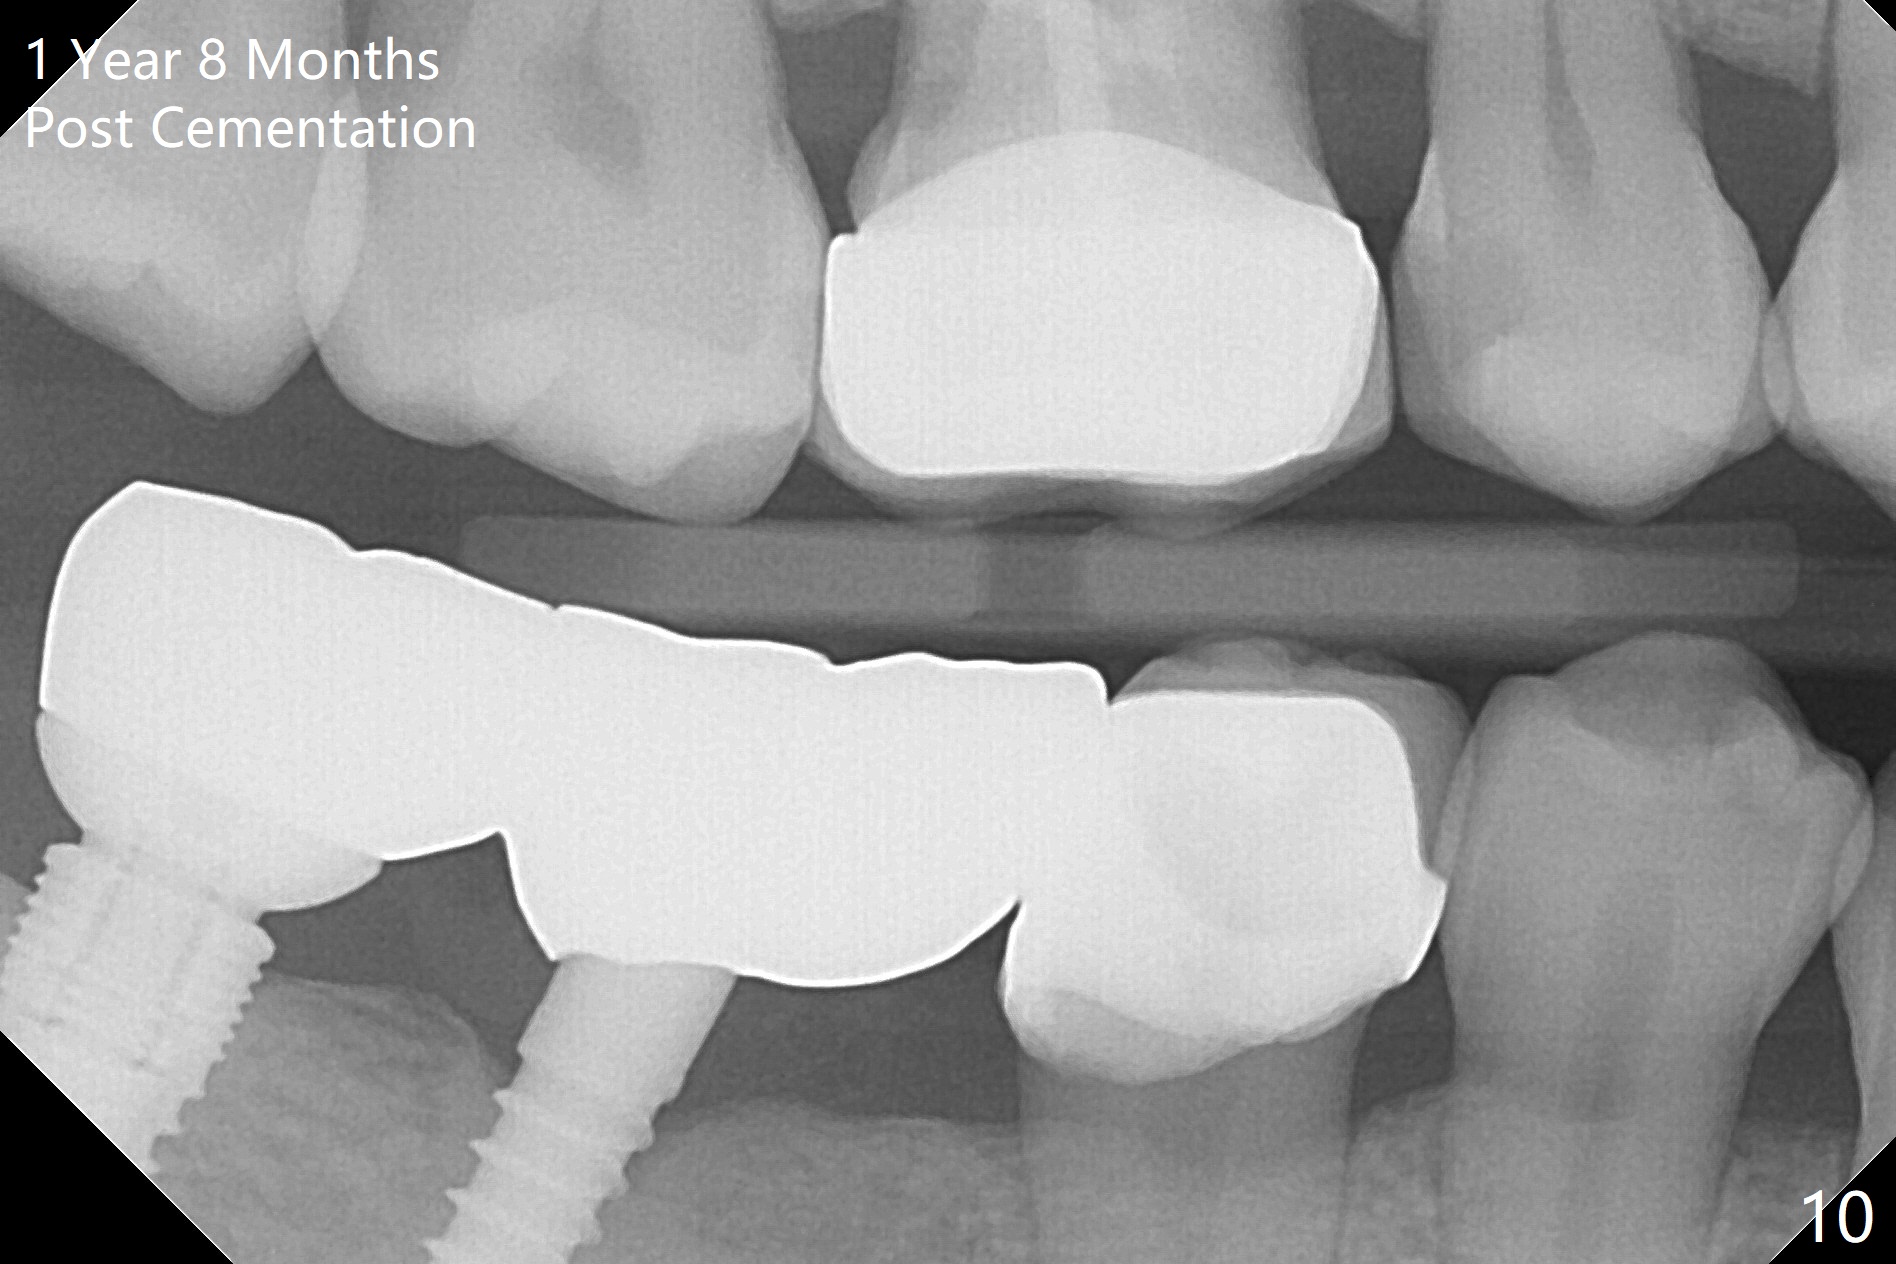

A preop photo shows different shape of pontics at #30 and 31 (Fig.1 <), suggesting different width of the edentulous ridge. Two of 8 mm parallel pins are inserted for position and trajectory (Fig.2 (red dashed line: the superior border of the Inferior Alveolar Canal). When they are removed from the osteotomy sites, the narrow ridge at #30 is shown (Fig.3). A 3x12 mm 1-piece implant is placed at #30, while a 4.5x10 mm 2-piece one at #31 (Fig.4,5). It appears that it is necessary to place an implant at #32, since the tooth #1 is present (Fig.5). The suggestion is rejected by the patient due to finance. After extraction of the tooth #32 and insertion of collagen plug, an immediate splinted provisional is fabricated to cover the #32 socket as well (Fig.6). The provisional is modified (to remove the portion that covers #32 socket) 3-4 weeks postop.

The patient returns for final restoration 3 months postop; bone resorption around the 1-piece implant is minimal (Fig.7). The definitive restoration is also splinted. The latter is further justified when the implant at #30 is found to be distal prior to cementation (Fig.8 *). It appears that implant spacing at the root level is more critical than parallelism, as compared to Fig.7. Let us improve this aspect. Bone loss around the implants remains minimal 7 months post cementation (Fig.9). It is the same 1 year 8 months post cementation (Fig.10), as compared to a cantilever FPD on the other side (Fig.11). The bone density around the implants at #30 and 31 increases 2 year 8 months post cementation (Fig.12).